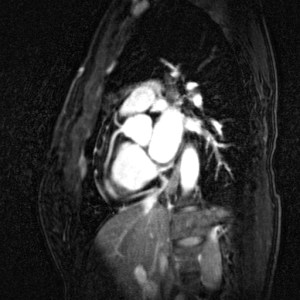

Νέα γυναίκα με μονήρη στεφανιαία αρτηρία, NSVT και συγκοπή

35χρονη γυναίκα, η οποία παρουσιάσθηκε με συγκοπή [οι περιστάσεις ήταν συμβατές με νευραγγειακή διαταραχή]. Στο Holter, όμως, βρέθηκε μη-εμμένουσα κοιλιακή ταχυκαρδία, και γι’ αυτό ξεκίνησε τυποποιημένη διερεύνηση.

CTA στεφανιογραφία και ΜRI

Διαγνωστικός καθετηριασμός (επιβεβαίωση της διάγνωσης) Συνέχεια ανάγνωσης «Νέα γυναίκα με μονήρη στεφανιαία αρτηρία, NSVT και συγκοπή»